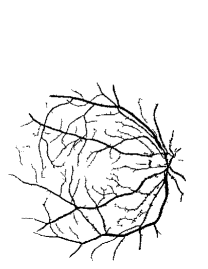

Refer to caption Refer to caption Refer to caption Refer to caption

(a)                                                                          (b)

(c)                                                                          (d)

Figure 9: Ground truth (left) and segmentation result (right): (a) and (b) are the images from DRIVE dataset, (c) and (d) are the images from the STARE dataset

V-B Vessel Segmentation Performance

The segmentation performance of the proposed model on three public available datasets is given in Table IV. It can be observed that the proposed model can achieve more than 95%percent9595\% segmentation accuracy on the DRIVE, STARE and CHASE_DB1 datasets, with the highest accuracy score Acc=96.0%𝐴𝑐𝑐percent96.0Acc=96.0\% achieved in the DRIVE dataset. Some exemplary segmentation results are shown in Fig.9. When treating the unknown regions as background regions, AUC=0.833 of trimap is 2.6%percent2.62.6\% lower than the proposed model while Acc of trimap is similar to the proposed model. In addition, Se=0.679𝑆𝑒0.679Se=0.679 of trimap is 5.7%percent5.75.7\% lower than the proposed model. These observations show that trimap can already have good segmentation performance, which indicates that the selection of region features is very effective in segmenting blood vessels. From Table IV, it can be observed that the model with vessel skeleton extraction can achieve more than 5%percent55\% increase of Sensitivity𝑆𝑒𝑛𝑠𝑖𝑡𝑖𝑣𝑖𝑡𝑦Sensitivity and 2%percent22\% increase of AUC𝐴𝑈𝐶AUC compared with the model without vessel skeleton extraction while Acc𝐴𝑐𝑐Acc of the model with vessel skeleton extraction is similar to the model without vessel skeleton extraction, which demonstrates the effectiveness of vessel skeleton extraction.